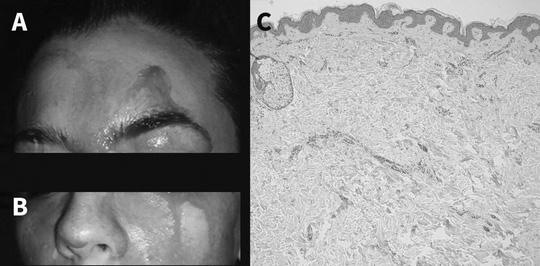

Theo báo cáo của Viện Nghiên cứu Quốc gia thuộc Trung tâm Truyền thông Sức khỏe di truyền và bệnh học (Ý), nữ bệnh nhân gặp tình huống này đã 3 năm, mỗi lần chảy máu kéo dài từ 1 đến 5 phút. Khuôn mặt và hai bàn tay cô lập tức đẫm máu tươi, y như trong các bộ phim kinh dị. Máu chảy nhiều hơn những khi cô đang căng thẳng.

Các bác sĩ đã chẩn đoán cô thực sự bị chảy máu cam do hiện tượng các mao mạch dưới da vỡ ra và thấm qua những vùng da hoàn toàn lành lặn. Một vài loại thuốc hướng thần được kê toa cho bệnh nhân, nhằm chống trầm cảm và giúp tâm trạng cô tốt hơn. Hiện tượng chảy máu có giảm nhưng vẫn không dừng lại.